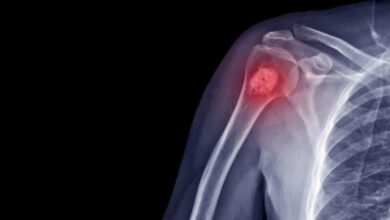

• التصوير بالأشعّة السينيّة: حيث يتم أخذ صورة للمفصل لاستبعاد الأسباب الأُخرى التي قد تتسبّب في حدوث التهابٍ في المفاصل.